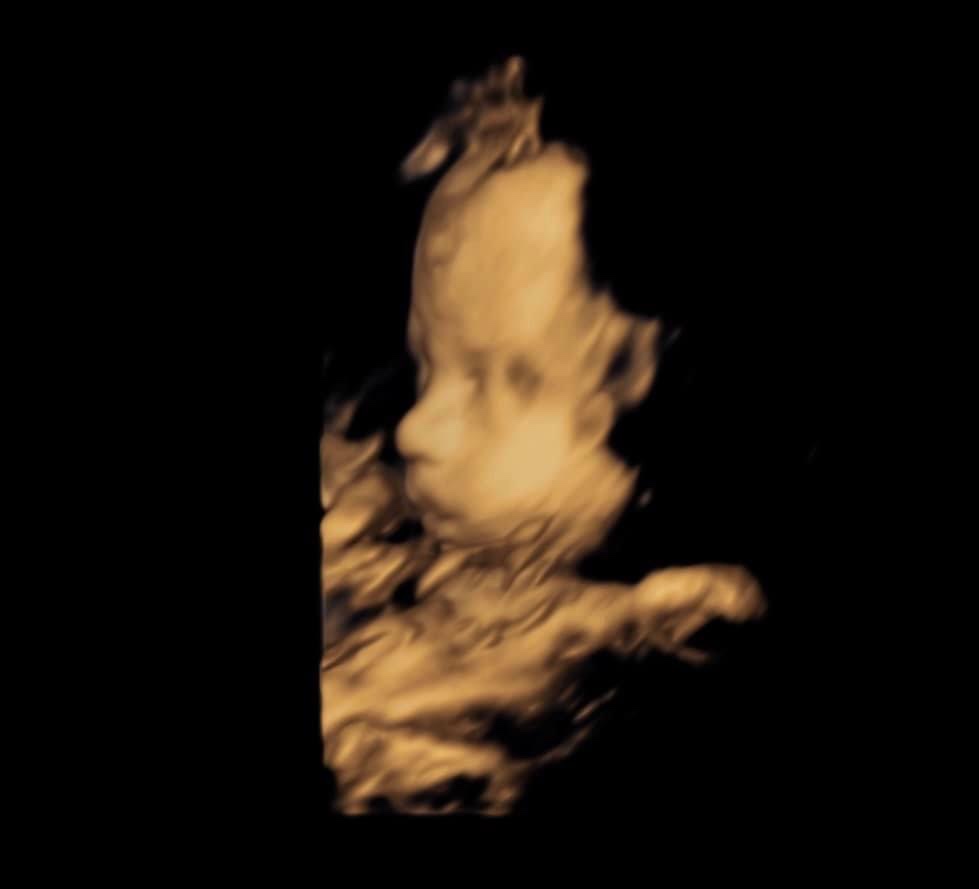

Amelia lived 38 weeks, 5 days in my womb and she lived 11 days after she was born. We are forever changed for having known and loved her.